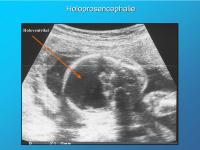

Holoprosencephalie

Abbildung 8

Keywords: